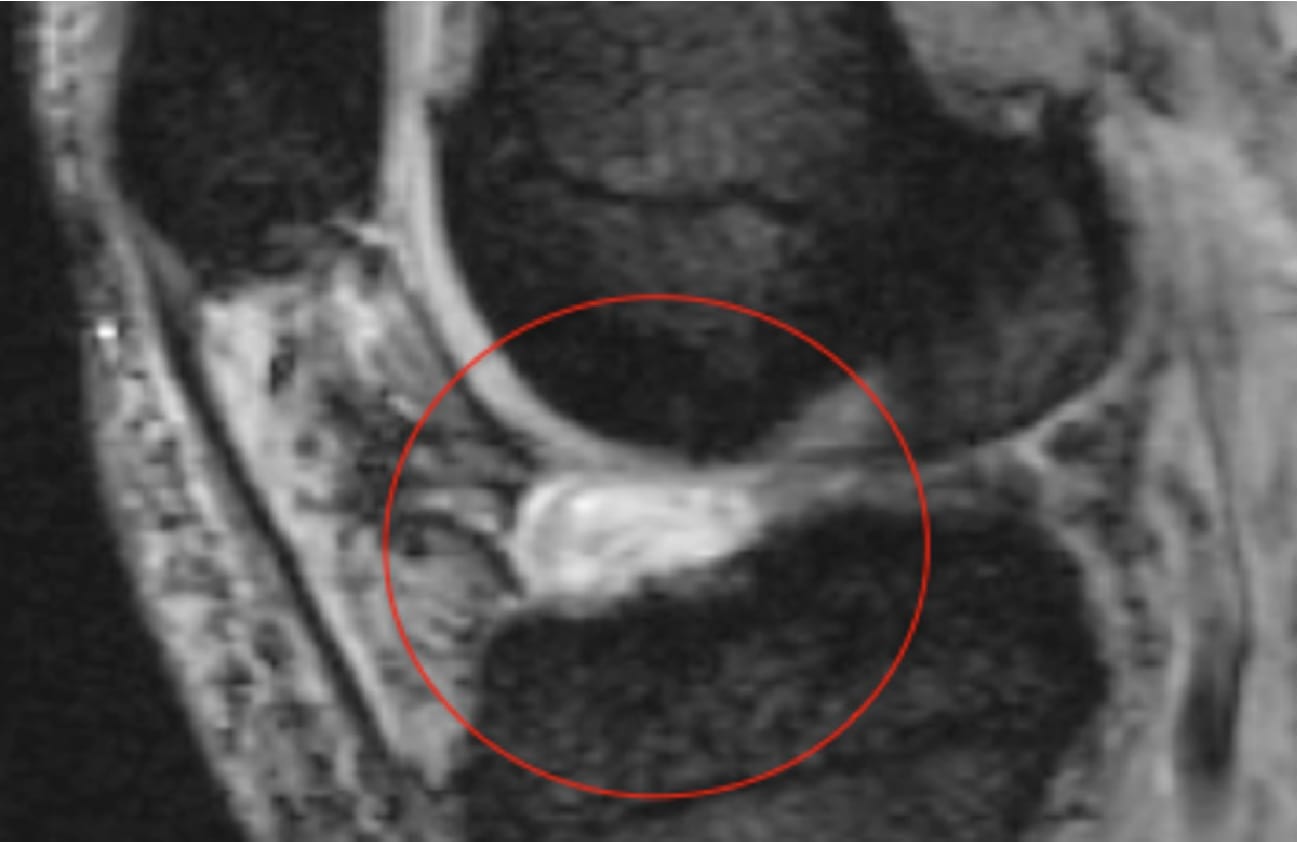

Badania obrazowe:

• MRI: uwidacznia blizny, zrosty wewnątrzstawowe i zmiany w torebce/mięśniach.